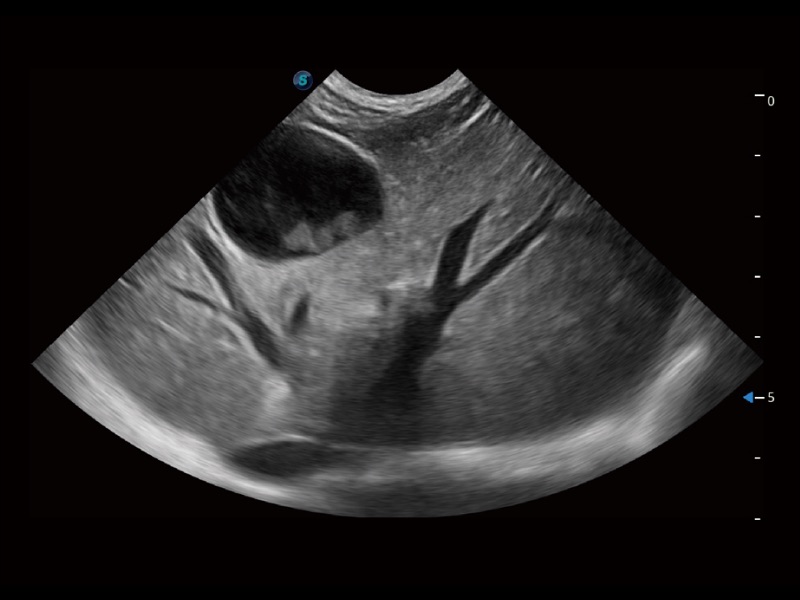

ProPet 70 进一步提升了微米成像算法,更加注重对基础原始图像的还原和保留,在有效减少斑点噪声、增强组织边界显示的同时,避免过度优化丟失真实的解剖信息。

增强穿刺针在动物解剖结构中的位置,提高穿刺介入的安全性和准确性。